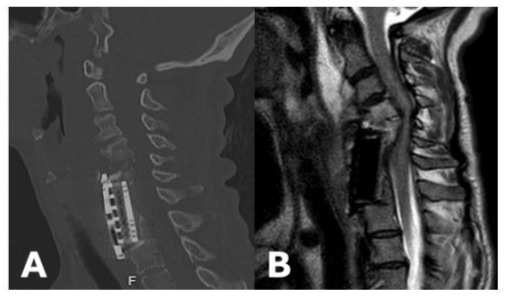

52-year-old male with past medical history significant for diabetes mellitus (DM), end-stage renal disease (ESRD), heart failure with preserved ejection fraction (HFpEF), deep venous thrombus (DVT) with inferior vena cava (IVC) filter presented to the hospital with a chief complaint of bilateral upper extremity (BUE) deltoid weakness with associated paresthesias and bowel incontinence for six days. Past surgical history significant for revision C3-C5 ACCF and C2-C5 posterior cervical fixation one month prior for methicillin-resistant staphylococcus aureus (MRSA) osteomyelitis. Cervical x-ray (XR) and computed tomography (CT) Cervical Spine discovered subsidence of the corpectomy hardware and cervical kyphosis resulting in retropulsion of the bone and hardware (Figure 1A and B). MRI Cervical Spine confirmed severe canal stenosis and draping of the spinal cord over the retropulsed fragment (Figure 1C). The patient was placed in cervical traction using Gardner-Wells tongs, which improved the cervical kyphosis and the patient’s neurologic exam. On hospital day (HD) one, the patient was taken to the operating room for revision corpectomy to include C3-C6 and extension of the posterior cervical construct. Post-operatively, the patient regained full strength and sensation. CT scan completed on post-operative day (POD) three demonstrated early subsidence and thus the patient was placed in a halo brace (Figure 2). Unfortunately, patient’s hospital course was complicated by worsening gastrointestinal bleeding and ultimately septic shock. He passed away one month following surgery.

Figure 1: Lateral XR (A) and Sagittal CT Cervical Spine without Contrast (B) Demonstrating severe subsidence of the cervical cage with retropulsion, C5 fracture, and the resulting severe kyphotic deformity. Sagittal T2 MRI Cervical Spine without Contrast shows severe cervical canal stenosis and draping of the cervical cord over the retropulsed fragment (C).

Figure 2: Post-operative lateral XR showing improved cervical alignment and the halo brace (A). Post-operative sagittal CT Cervical Spine without Contrast demonstrating proper position of anterior and posterior hardware (B).